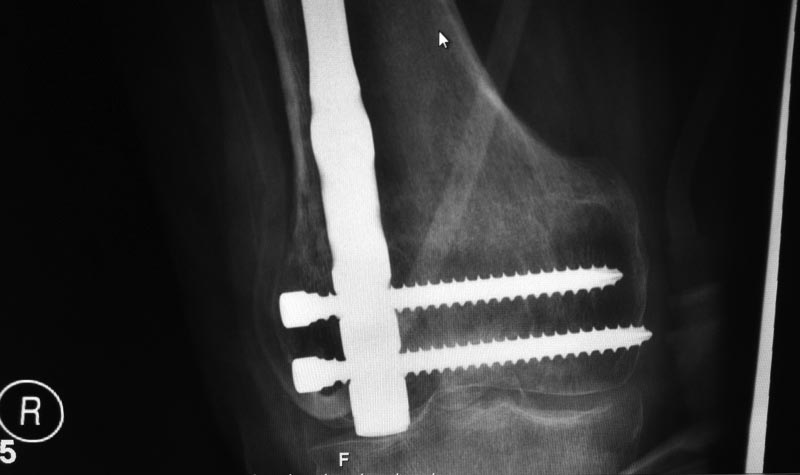

Доброго времени суток . Больной ( 35лет ) дважды оперирован после ДТП от марта 2012 пластинами с угловой стабильностью в том числе мостовидной мыщелковой пластиной . Обе конструкции сломал при этом соблюдал предписаный режим. 2 недели назад прооперирован в одной из клиник Санктпетербурга . укорочение минимальное 1 см ротационных смещений нет .Коленный сустав перестал сгибаться . Что делать дальше . больной морально и финансово истощен . ждать сращения а затем вставать на квоту на эндопротезирование коленного сустава .сейчас БОМБЕЙСКАЯ мсэ дала 3 гр инвалидности . РАботать мужчина не может . Не спрашиваю кто виноват ,что делать дальше .

еще снимки

1. Боковая проекция где?

2. Удалить гвоздь и ресинтезировать адекватно с исправлением оси и заходом через межмыщелковую вырезку. Как исправлять ось - на форуме много раз обсуждалось: можно в аппарате, можно с помощью поллеров.

P.S. после такого синтеза суставу определенно кирдык. (Извините за жаргон, но через латеральный мыщелок ввести ретроградный гвоздь...) Здесь можно было и антеградно сделать, не "вскрывая" сустав.

Гвоздь в суставе стоит - с чего бы ему(суставу) сгибаться...

Судя по количеству "следов" от винтов и их расположению, нарушены принципы фиксации пластинами с угловой стабильностью. Можно распотрошить зону перелома, девитализировать отломки, и потом долго удивляться: почему это не срастается? И остеомиелит скорее всего здесь не причем.